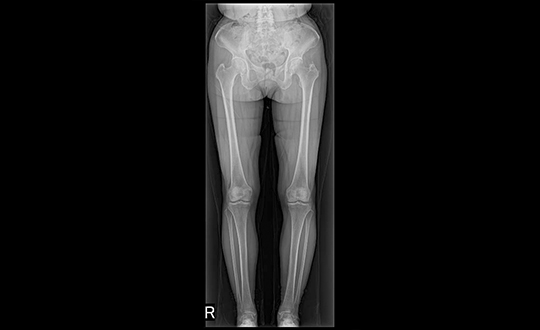

デジタル技術により高画質と低被ばくを両立したレントゲン装置。ISS方式の自動撮影条件設定や長尺撮影に対応し、全脊椎・全下肢の一括撮影も可能。短時間で体への負担が少ない検査を行います。

関節疾患、スポーツ障害、骨折など、幅広い症例に対応可能で、患者様一人ひとりに合わせた治療方針を提案しています。術前検査から術後フォローまで一貫した対応が可能であり、地域の先生方との連携のもと、必要な症例に対し迅速かつ的確に対応します。